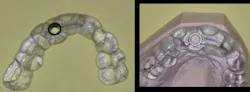

If you are placing implants, using a surgical guide to assist in placing some of the implants is relatively easy, not very expensive, and certainly helpful for a practitioner who is just learning to place implants (figures 1 and 2).

Figures 1 and 2: This cast represents a patient who has two missing maxillary lateral incisors. The surgical guide was made as an educational model showing use or nonuse of a guide. One of the implants was placed using a guide and the other missing tooth was replaced using freehand implant placement. Surgical guides are very valuable for practitioners just beginning implant placement and for complicated clinical situations, but most implants are placed freehand using radiographs as a visual guide.